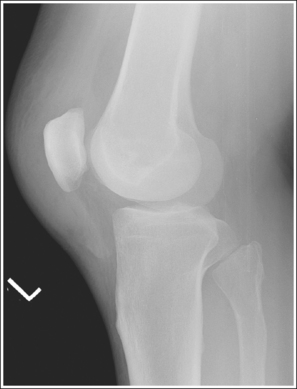

See Figures 6-80 and 6-81 and Box 6-17.

Contrast and density are adequate to demonstrate the suprapatellar fat pads.

• Suprapatellar fat pads. Two soft tissue structures of interest at the knee are used to diagnose joint effusion and knee injury. They are the posterior and anterior suprapatellar fat pads. Both are located anterior to the patellar surface of the distal femur and are separated by the suprapatellar bursa (Figure 6-82). Fluid that collects in the suprapatellar bursa causes the anterior and posterior suprapatellar fat pads to separate. It is a widening of this space that indicates a diagnosis of joint effusion.

The patella is situated proximal to the patellar surface of the femur, and the patellofemoral joint is open.

• The knee should be flexed 10 to 15 degrees. With less than 20 degrees of knee flexion, the patella is situated proximal to the patellar surface of the femur, the quadriceps are relaxed, and the patella is fairly mobile. In this patellar position the anterior and posterior suprapatellar fat pads can be easily used to evaluate knee joint effusion. Conversely, when the knee is flexed 20 degrees or more, a tightening of the surrounding knee muscles and tendons is present, the patella comes into contact with the patellar surface of the femur, and the anterior and posterior suprapatellar fat pads are obscured, eliminating their usefulness in diagnosing joint effusion (see Image 67). Some authors indicate that 20 to 30 degrees of knee flexion should be used on a lateral knee projection. Facility routines dictate the actual number of degrees that should be used.

The distal articulating surfaces of the medial and lateral femoral condyles are superimposed, and the knee joint space is open.